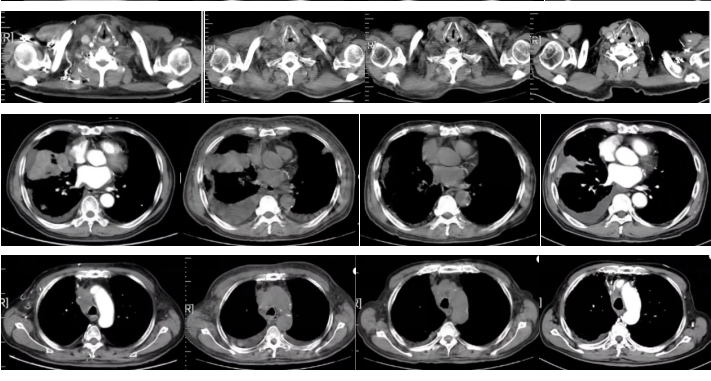

图3

2022-09-17胸部平扫CT:恶性肿瘤维持性化学治疗后,较2022-7-20胸部CT旧片,右肺中叶占位(7.3×4.4cm)缩小;双肺部分结节增大;纵隔及右肺门淋巴结缩小;主动脉左侧旁(2-22)淋巴结稍增大:右侧胸腔积液增多;左侧新增胸腔积液;胸壁水肿增厚,双侧腋窝小淋巴结,请结合临床;余未见显著变化。附见,胰尾较前稍增粗:肝S4段新增低密度小结节,请结合腹部相关检查。

疗效评价:SD。

2022-11-16胸部平扫CT:恶性肿瘤维持性化学治疗后,较2022-9-16日胸部CT,右肺中叶占位(2.2×1.9cm)缩小;双肺大部分结节消失;右侧胸腔积液减少,左侧胸腔积液消失;纵膈及双侧腋窝淋巴结缩小;扫描层面内肝脏结节本次未见明确显示,胰腺结节缩小;余较前变化不大。

疗效评价:PR。

2023-02-28胸部+上下腹增强CT:恶性肿瘤维持性化学治疗后,较2022-11-15日胸部CT,右肺中叶斑片影范围增大;右肺门淋巴结增大;右侧胸腔积液增多:心包积液减少;双肺间质性改变同前,余较前变化不大。胰尾旁多发结节,考虑MT可能。肝门区及腹膜后淋巴结稍大。左侧肾上腺结节样增厚,双侧部分肋骨、右侧髂骨高密度影,建议定期复查。肝S7段脂肪瘤。

图4